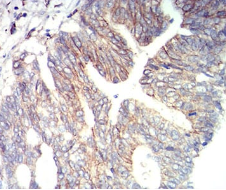

CD166 Mouse Monoclonal antibody[2F112]

This gene encodes activated leukocyte cell adhesion molecule (ALCAM), also known as CD166 (cluster of differentiation 166), which is a member of a subfamily of immunoglobulin receptors with five immunoglobulin-like domains (VVC2C2C2) in the extracellular domain. This protein binds to T-cell differentiation antigene CD6, and is implicated in the processes of cell adhesion and migration. Multiple alternatively spliced transcript variants encoding different isoforms have been found.

IHC    1/200 - 1/1000